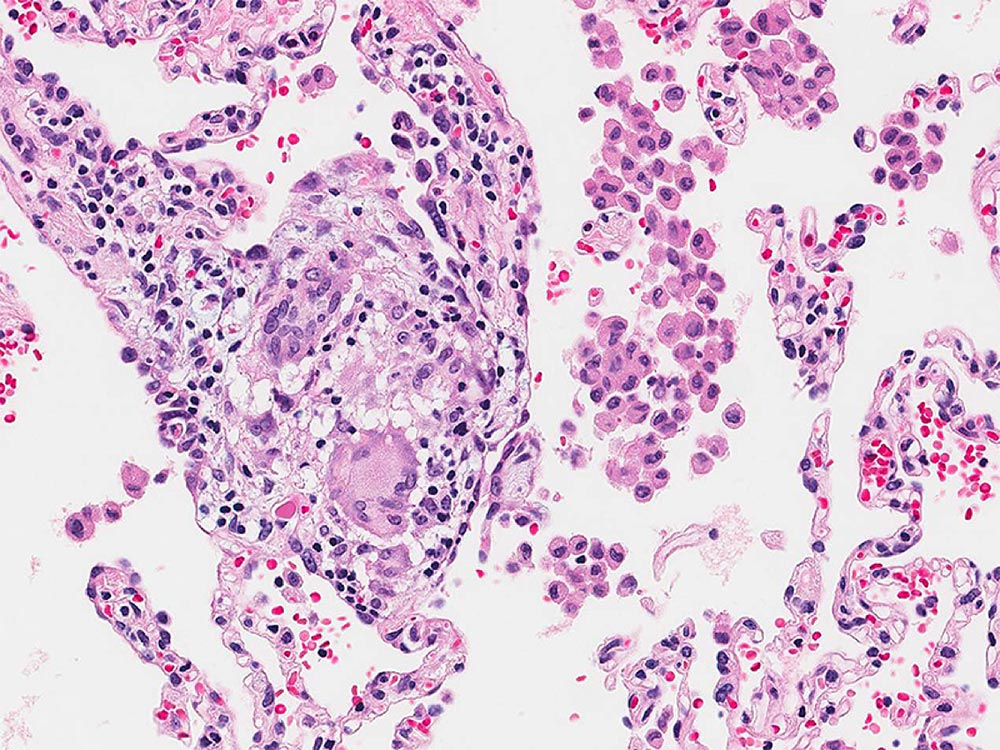

High resolution photomicrograph illustrating small interstitial granulomas typical of hypersensitivity pneumonitis.

Image courtesy of and used with permission from Kirk Jones, MD.